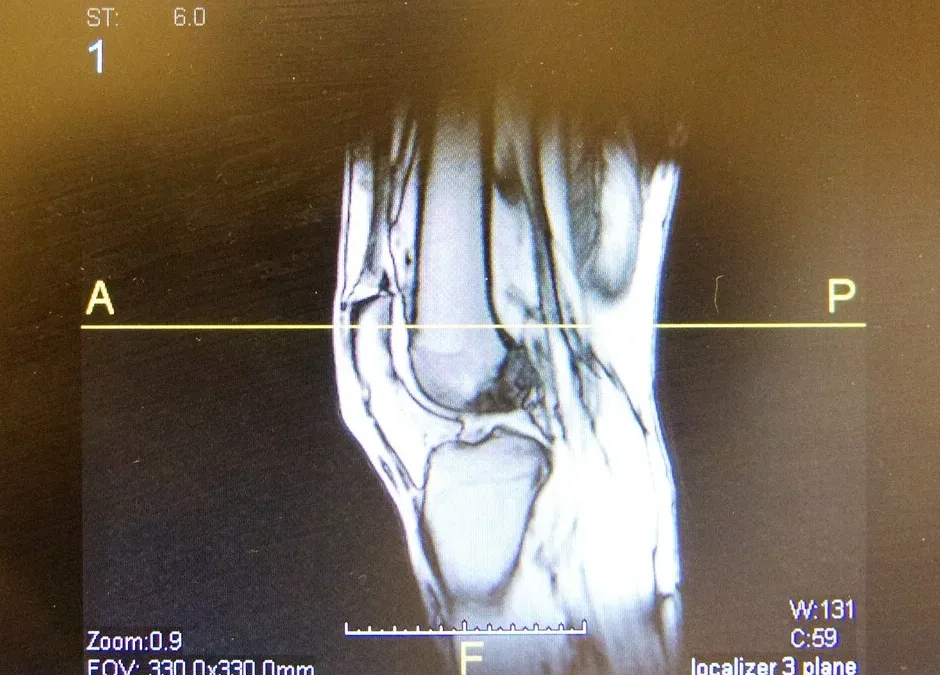

The ACL is one of the key stabilising ligaments of the knee, crucial for controlling rotation and forward movement of the tibia. An ACL rupture typically occurs during sudden changes in direction, pivoting, or awkward landings — common in sports like AFL, soccer, basketball, and netball. It most often affects young, active individuals, particularly females, due to biomechanical and hormonal factors. While not all ACL injuries require surgery, those with complete ruptures who wish to return to cutting or pivoting sports usually undergo ACL reconstruction. Regardless of the surgical decision, structured rehabilitation guided by a physiotherapist is essential for a successful recovery and long-term knee health.